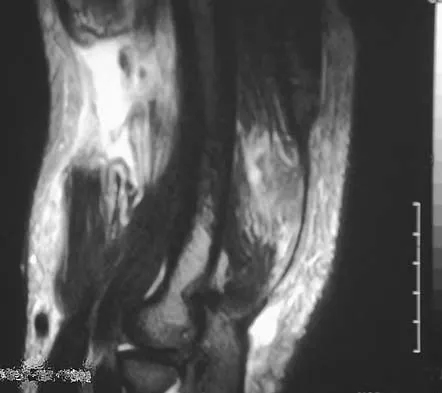

A 20-year-old man sustained an injury to his arm during a tug-of-war contest. An MRI scan is shown in Figure 18. What is the most likely diagnosis?

Explanation

The MRI scan reveals a transection of the biceps muscle. The underlying brachialis is intact. This injury can occur as a result of a cord wrapped around the upper arm. Care should be taken to ensure that there is no concurrent vascular injury. A posterior subcutaneous lipoma appears as a well-encapsulated mass on T2-weighted images. Heckman JD, Levine MI: Traumatic closed transection of the biceps brachii in the military parachutist. J Bone Joint Surg Am 1978;60:369-372.